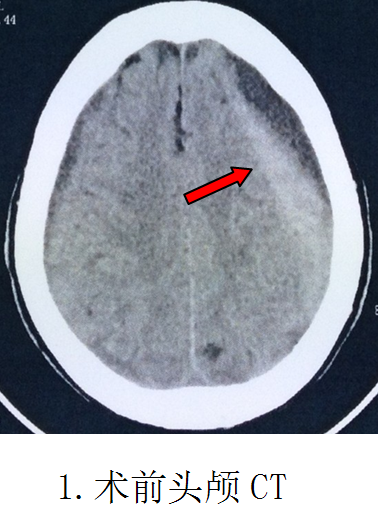

阿婆是在8天前因头痛查因住进医院的。当时头痛、精神差伴右侧肢体乏力1周,头部CT检查确诊“左侧额颞顶巨大慢性硬脑膜下血肿”,量约100多毫升。追问阿婆1个月前有头部外伤史。医生建议手术治疗。但是阿婆已经98岁高龄了,家属担心无法挺过手术关。医学常规认为,超过70岁以及70毫升以上的颅内血肿,手术是必须慎重的。阿婆98岁100多毫升的血肿,对于外科医生是一个考验。这也是我院神经外科至今遇到最高龄的一位手术患者了。如果在前几年,对于阿婆的手术,我们也是犹豫的。

第二天即实施手术,在局部麻醉清醒状态下,顺利实施了微创手术“双管硬通道微创钻孔冲洗引流术”,头皮只有两个0.3厘米直径的点状钻孔穿刺损伤,术中冲洗出血肿100多毫升,整个手术时间仅需30分钟。复查CT血肿完全清除,手术成功。当天晚上病人精神明显好转,偏瘫的右手即能抬起来跟医生握手。第5天下床行走,偏瘫肢体完全康复,取得立竿见影的效果。第8天顺利出院。